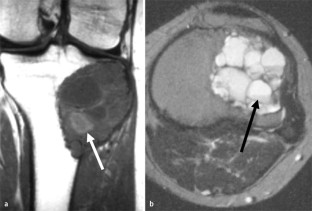

MRI morphology of bone tumors and tumor-like lesions

Für das Staging und die Charakterisierung von Knochentumoren und tumorähnlichen Läsionen ist in der Magnetresonanztomographie (MRT) der Einsatz von Spinechosequenzen erforderlich. Die MRT hat nur einen geringen Stellenwert in der Bestimmung der Dignität. Obwohl viele Knochentumoren und tumorähnliche Läsionen eine vergleichbare Morphologie in dieser bildgebenden Modalität aufweisen, können einige Tumorentitäten mittels MRT recht zuverlässig diagnostiziert werden. Hierzu zählen Knorpeltumoren, die solitäre und aneurysmatische Knochenzyste, der Riesenzelltumor, fetthaltige Läsionen und bis zu einem gewissen Grad auch das Osteoidosteom und das Osteoblastom. Es werden praktische Tipps gegeben, wann bei Tumorverdacht die MRT eingesetzt werden sollte, wie bei einem zufällig bei einer MRT gefundenen Tumor die Untersuchung modifiziert werden sollte und welcher Tumor vorliegen könnte.

Spin-echo sequences are mandatory at MRI for staging and characterization of bone tumors and tumor-like lesions. MRI is of minor value in the estimation of the malignant potential of an osseous lesion. Although many bone tumors and tumor-like lesions present similar morphology at MRI, some entities can be diagnosed with good reliability. These include chondrogenic tumors, solitary and aneurysmal bone cysts, giant cell tumors, lesions containing fatty tissue and, to a certain extent, osteoid-osteomas and osteoblastomas. Practical advice is given regarding when to perform a MRI study in cases of tumor suspicion. Further advices are given for cases a tumor is found incidentally at a MRI study, how to modify the study and which kind of tumor may be present.